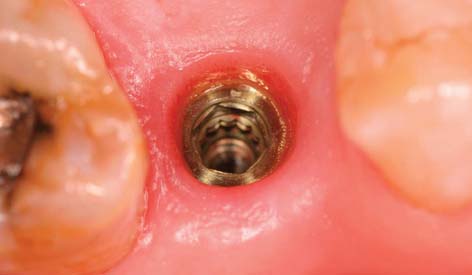

Treatment planning for the single tooth restoration, particularly in the anterior esthetic zone, is one of the most challenging problems faced by the implant restorative dentist. Placement of the implant for both esthetics and biomechanical loading (to minimize screw loosening) is especially crucial. In addition, at the treatment planning stage, the decision to place an implant with an antirotational feature built into the system (e.g., a spline or a hexagon) is essential (Fig. 13-18).

When the abutment is placed, the superstructure must be completely seated on the implant body without gaps or intervening tissue. In systems with antirotational facets in the implant (see Fig. 13-18), these features must be aligned to allow complete seating of the abutment. Thesuperstructure–implant body interface should be evaluated radiographically immediately after the uncovering. If a gap is present, the superstructure must be repositioned.